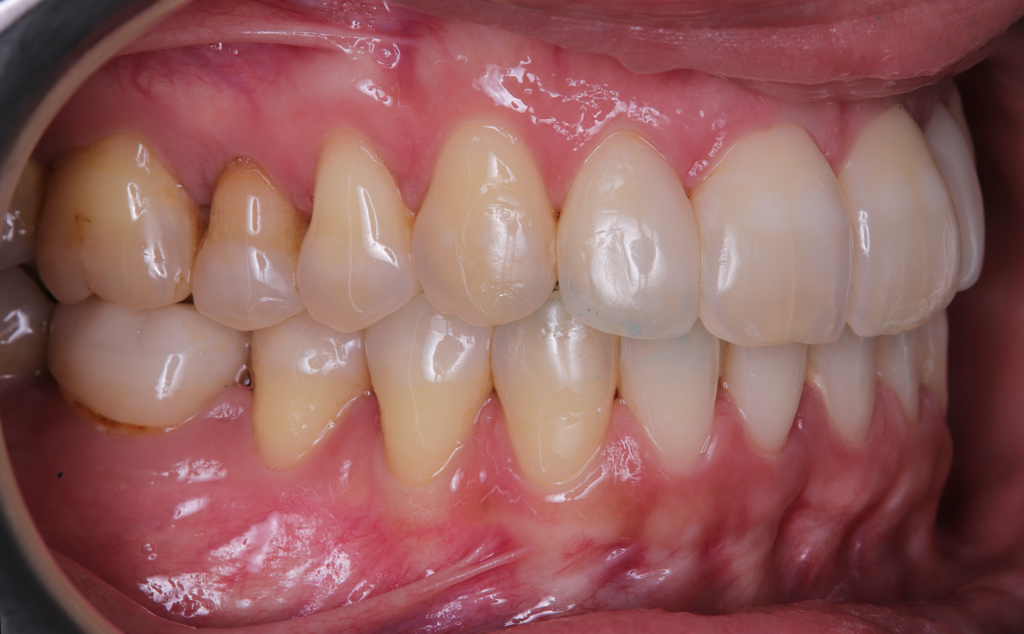

The patient, having completed a periodontal treatment phase, presented with significant aesthetic and functional concerns due to moderate crowding in both arches and a pronounced anterior crossbite. Clinical examination confirmed the need for comprehensive realignment, particularly in the anterior region. Although the patient had a history of periodontal issues, radiographic evaluation showed no signs of active disease. Based on these findings, the treatment plan was designed to carefully modulate orthodontic forces to protect the occlusion and surrounding tissues while addressing the misalignment.

To correct the misalignment and anterior crossbite without compromising tissue stability, a slower orthodontic treatment plan was devised using the Spark Advanced clear aligner system. The initial phase involved 36 aligners designed to gently expand and realign the dental arches, limiting the rate of tooth movement. Strategic interproximal reduction (IPR) was performed in the anterosuperior region (between teeth #21 and #11) to create the necessary space for proper alignment while avoiding excessive loading on the tissues.

A crucial aspect of the treatment was reducing the speed of tooth movement by 50%. This approach allowed a gradual application of orthodontic forces, giving the occlusion and tissues ample time to stabilize following the periodontal phase while effectively addressing the crowding and anterior crossbite.

At the conclusion of the treatment, the patient achieved excellent dental alignment and a stable occlusal relationship, particularly in the anterior region. Radiographs and clinical assessments confirmed that there was no further bone loss and that previous improvements were maintained. The aesthetic enhancement from the composite restorations further contributed to the overall success of the treatment.